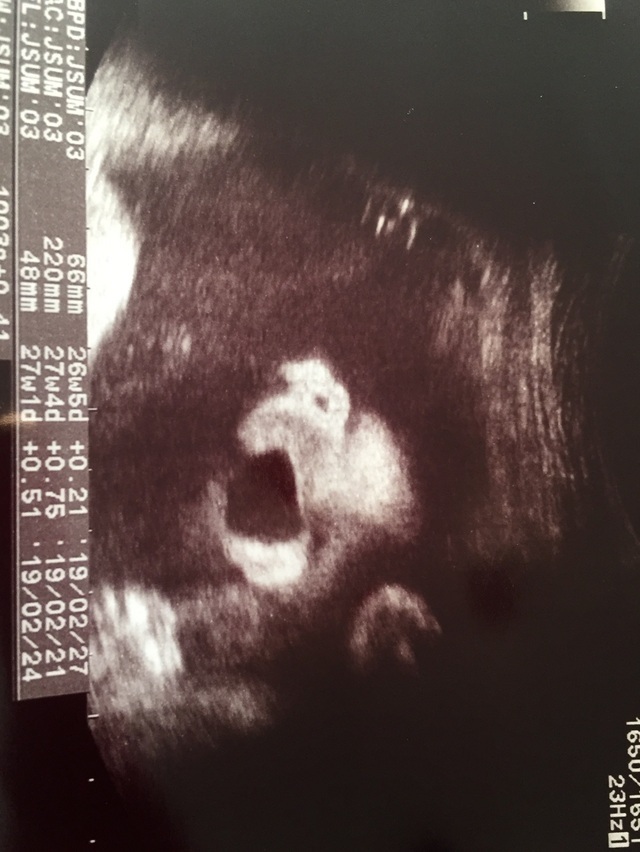

26週3日(26w3d・男の子)|ちゃも☆ さん(40歳)

エコー写真撮影時のエピソード:

鼻の穴をみせながらの大あくび。可愛くて診察中に笑っちゃいました。

『先生にも奇跡のショットだよ』と言われました!

パパには帰宅後見せましたが、感動した様子。小さな胎動をなんとなく感じていた時期だったので、エコー写真の元気な様子にふたりで安心したことを覚えています。